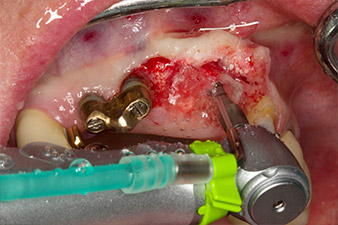

Following primary healing, the soft tissues were shaped using the basally lined bridge. Two months later the site was exposed by a slightly palatal alveolar ridge incision (Fig 2). The dimensions of the alveolar bone proved to be sufficient at position 22. Figures 2 and 4 show the preparation of the implant bed, the tapping and the implantation using Implantmed.

In order to compensate for the periodontal bone loss and achieve an aesthetically pleasing result, the implantation was combined with guided bone regeneration (GBR) with xenogenic replacement material and a collagen membrane

(Fig. 5 and 6).